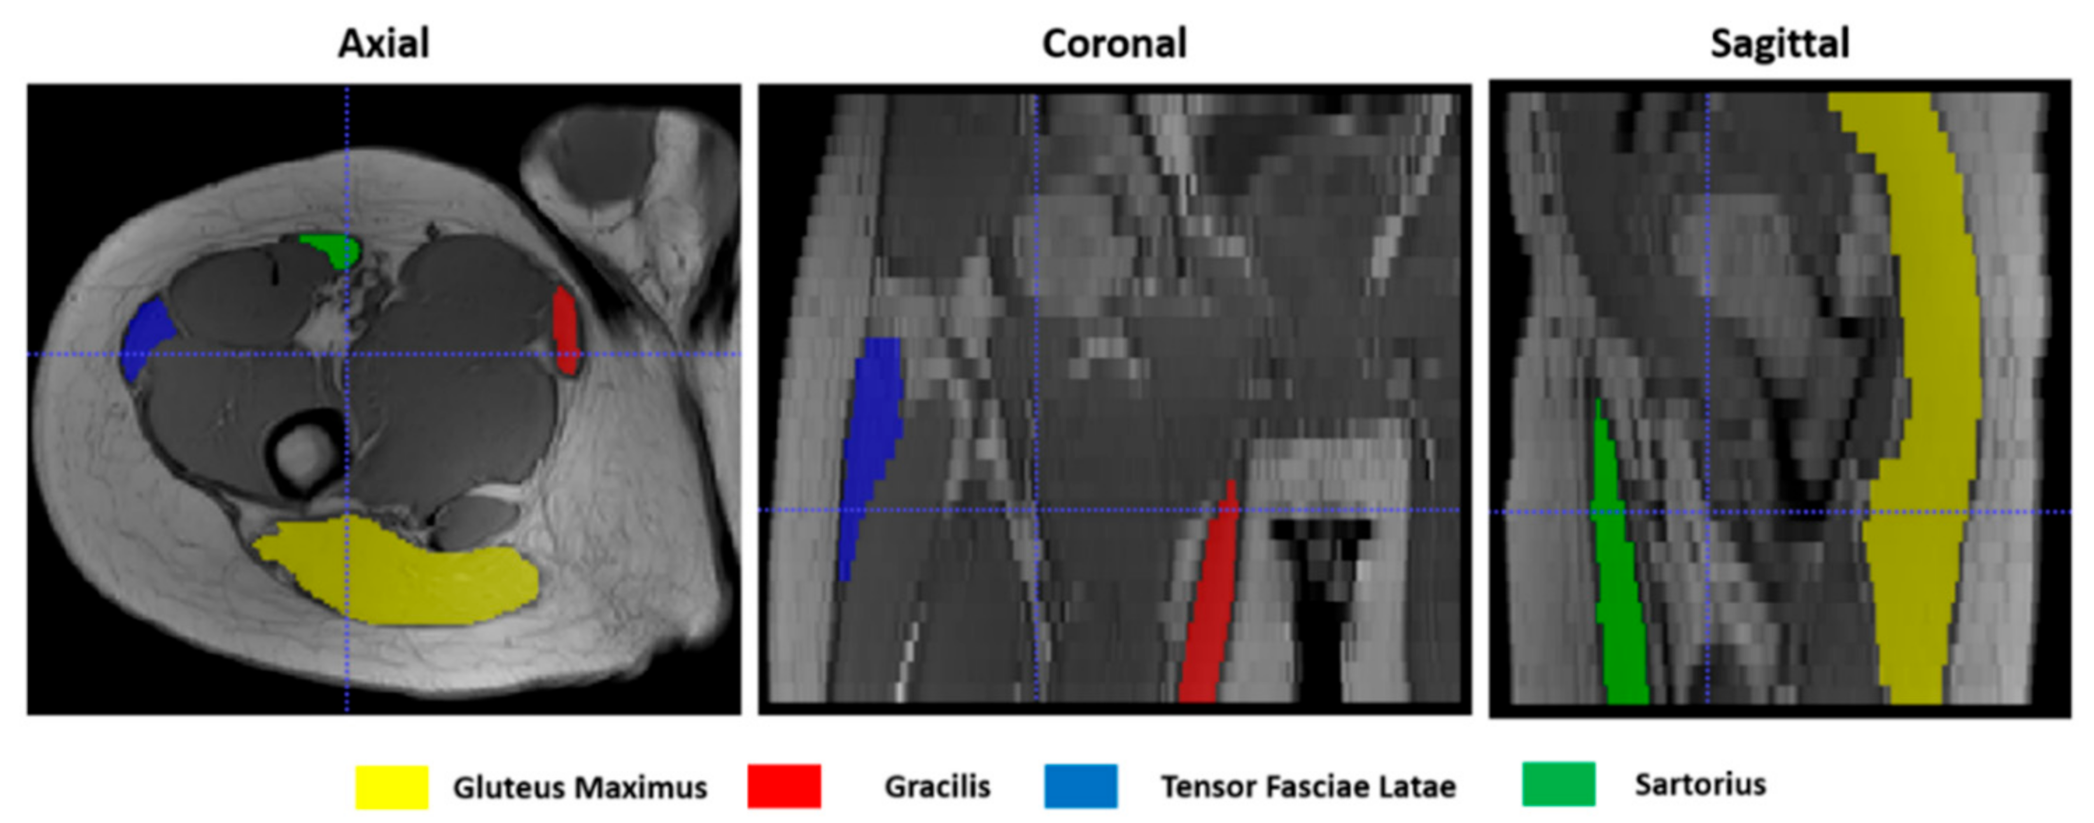

To give a quantitative assessment of the transformation accuracies, the surfaces of 4 representative hip muscles—gracilis, sartorius, gluteus maximus, and tensor fasciae latae—were manually delineated, slice by slice, on the T1w images (Figure 4) at both t0 and t1 separately with ITK-Snap [34]. Region of Interests (ROIs) volumes are listed in Table 1. Contours on t1 were then automatically deformed on the corresponding t0 volumes using the resulting transformation of each registration. Nearest-neighbor interpolation was applied to keep the integer values of the original labels.

Figure 2. An example of the results of the masking step on T1-w MR images in 3 orthogonal views.

Figure 4. Muscle ROIs delineation on T1-w MR images in 3 orthogonal views.